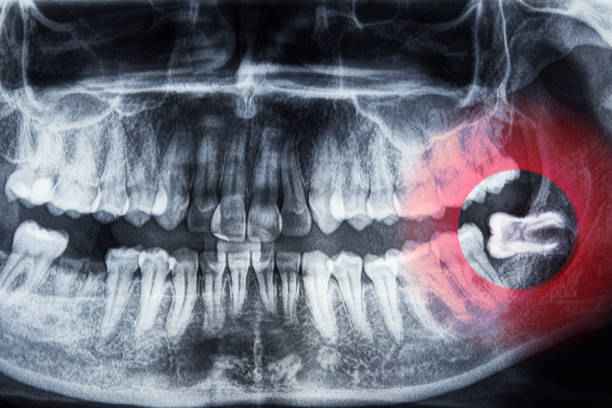

ما هي أعراض ضرس العقل ؟

تختلف أعراض ضرس العقل من شخص لآخر، وقد تظهر بشكل تدريجي أو مفاجئ تبعًا لطريقة بزوغه وموقعه داخل الفك، وفي كثير من الحالات تكون المتابعة داخل عيادة اسنان الدمام ضرورية لتجنب المضاعفات.

- الشعور بألم متكرر أو نابض في الجزء الخلفي من الفك، وقد يمتد هذا الألم إلى الأذن أو الرأس مسببًا صداعًا مزعجًا يؤثر على التركيز والنوم.

- تورم اللثة المحيطة بضرس العقل مع احمرار واضح وإحساس بالضغط، خاصة عند المضغ أو فتح الفم.

- صعوبة في فتح الفم بشكل طبيعي نتيجة الالتهاب أو التشنج العضلي المصاحب لبزوغ الضرس.

- رائحة فم غير مستحبة أو طعم مر نتيجة تراكم البكتيريا وبقايا الطعام في المنطقة الخلفية التي يصعب تنظيفها.

- التهاب متكرر في اللثة قد يترافق مع ارتفاع طفيف في درجة الحرارة والشعور بالإرهاق العام.

- ازدحام الأسنان المجاورة أو الشعور بتغير في انتظامها بسبب الضغط الناتج عن بزوغ الضرس.